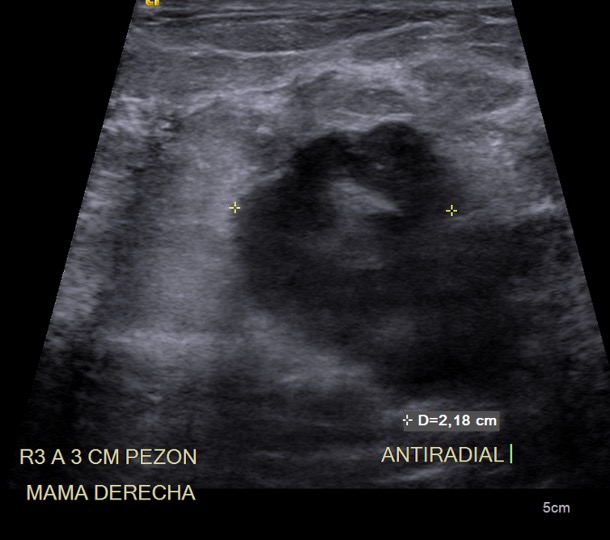

Imágenes de ecografía mamaria derecha con tranductor lineal (A, B, C), y a nivel subclavio derecho (D) y en región axilar derecha (E).

F. Mama derecha heterogénea, por la presencia de nódulo de composición sólida, homogénea, con realce periférico tras la administración de medio de contraste, localizado hacia cuadrantes internos y medidas aproximadas de 28×41 mm.